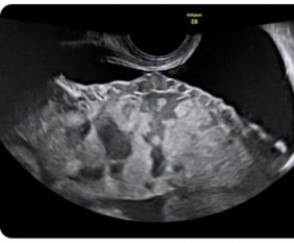

* Siêu âm Doppler màu: có 3 tiêu chuẩn chính:

- Tiêu chuẩn 1: mất khoảng sáng sau bánh rau hoặc khoảng sáng sau bánh rau

< 2 mm, kèm theo không thấy mạch máu chạy song song với lớp đáy, có các mạch máu chạy thẳng góc về phía cơ tử cung [30].

- Tiêu chuẩn 2: hình ảnh các xoang chứa dịch trong nhu mô của bánh rau ở vùng mà bánh rau ăn vào thành tử cung, hình ảnh Doppler mạch máu những xoang này thường là các xoang mạch (có phổ màu) [30].

Hình 1.2: Hình ảnh xoang mạch máu trong bánh rau [14]

- Tiêu chuẩn 3: mất hình ảnh khoảng ranh giới giữa cơ tử cung và thành bàng quang, lớp cơ tử cung mỏng < 1 mm, thành bàng quang bị đẩy lồi vào trong lòng của nó (dấu hiệu giả khối u) [30].

Theo các tiêu chuẩn mô tả trong Y văn thì tiêu chuẩn 1 và 2 gặp ở 100% số trường hợp, trong đó hình ảnh siêu âm 2D có các nang chứa dịch nằm trong nhu mô rau là dễ dàng nhận ra nhất và có giá trị cho chẩn đoán thậm chí từ rất sớm, các dấu hiệu khác thì khó nhận ra hơn trên siêu âm, đó là thành tử cung lồi vào trong lòng bàng quang (dấu hiệu giả khối u).

Một số nghiên cứu trên thế giới về vấn đề này cũng có những nhận định tương tự nhưng nếu chỉ có một tiêu chuẩn thì độ nhạy là 100% nhưng giá trị tiên đoán (+) chỉ là

48%, có hai tiêu chuẩn thì độ nhạy là 80% và giá trị tiên đoán (+) là 86%, còn hình ảnh các nang chứa dịch trong nhu mô rau thì có độ nhạy là 93%, thấp nhất trong các dấu hiệu siêu âm là mất khoảng sảng sau bánh rau thì độ nhạy là 7% và giá trị tiên đoán (+) là 6%, nhưng kết hợp dấu hiệu mất khoảng sáng sau bánh rau với các dấu hiệu siêu âm khác thì độ nhạy là 73% và giá trị tiên đoán (+) là 85% [30].

Đối với siêu âm Doppler màu trong nghiên cứu của Trần Danh Cường [27] đều thấy, có hình ảnh đặc trưng là các mạch máu đi thẳng góc với thành tử cung, hình ảnh các xoang mạch trong nhu mô rau gặp ở 100% số ca. Nghiên cứu trên thế giới cũng chỉ ra rằng, Doppler màu rất có giá trị trong chẩn đoán RCRL với độ đặc hiệu là 96,8%, độ nhạy 87,5%, giá trị tiên đoán (-) là 95,3% và giá trị tiên đoán (+) là 87,5% [30].